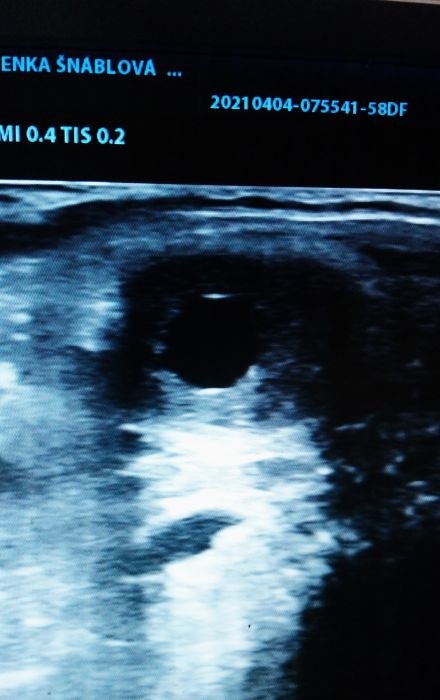

Dominantní folikul krátce před ovulací

Přesné zjištění ovšem bez dalšího následného USG vyšetření není možné, je tedy třeba USG vyšetření opakovat. Vím, že se opakuji, ale tohle je velmi důležité: při inseminaci chlazeným (čerstvým) semenem není potřeba vyšetření USG mnoho, ale je důležité po inseminaci zkontrolovat, zda klisna zovulovala. Při inseminaci mraženým semenem se USG vyšetření provádí přibližně každých 6 hodin (bavíme se o době těsně před ovulací, kterou předpokládáme dle velikosti a stavu folikulu 4,5 a více cm). V ideálním případě si zkušený technik pohlídá ovulaci klisny tím, že při velikosti folikulu cca 3,5 – 4 cm aplikuje hCG. K vlastní inseminaci pak dochází v době před ovulací (čerstvé semeno), v případě využití mraženého semene pak ideálně těsně před či po ovulaci. Pokud máme klisnu po ovulaci (zjištěno USG), další vyšetření, nyní již na graviditu, lze provést již od 13. dne, ideálně však 16. den po ovulaci, kdy dochází k tzv. nidaci oplozeného vajíčka, tj. uchycení na jednom místě v děložní sliznici.